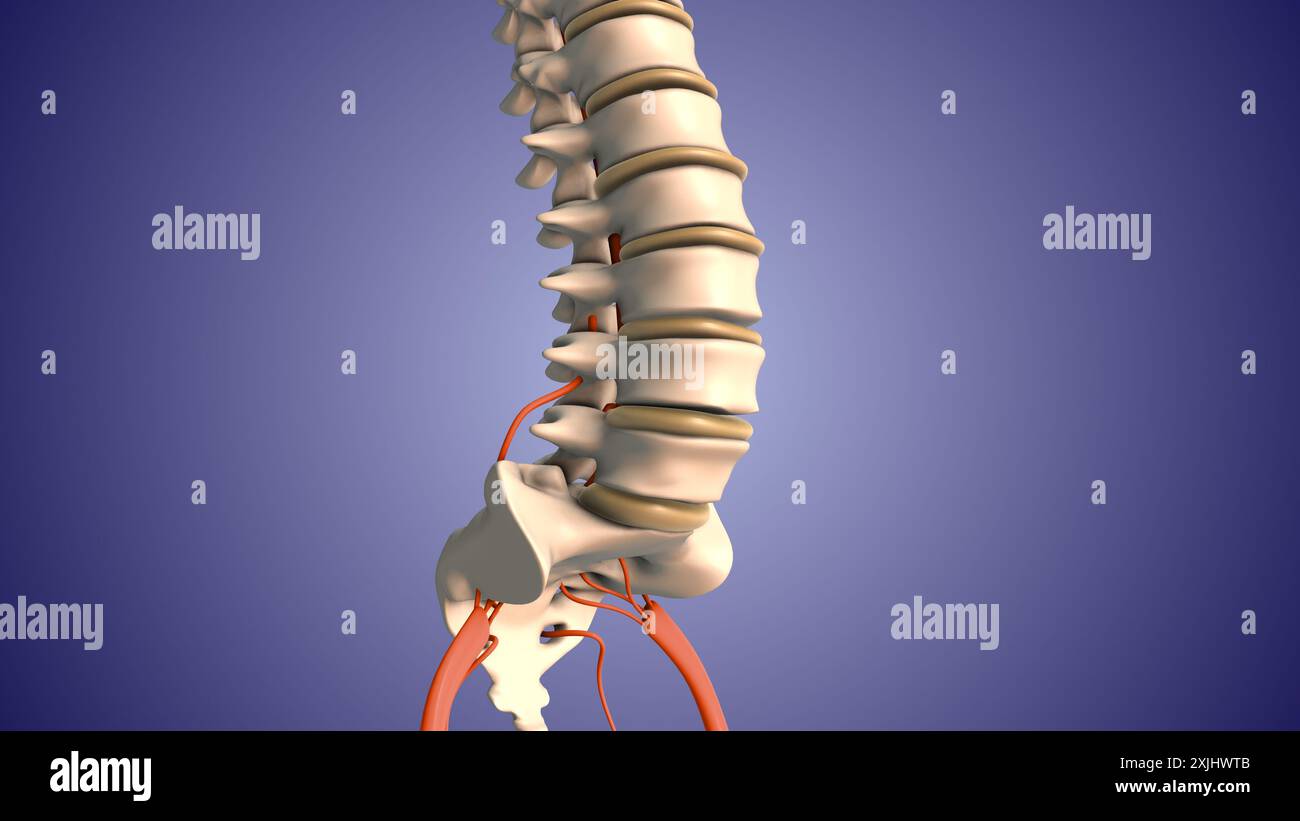

Nervenschmerzen des Ischias im Unterkörper Stockfotohttps://www.alamy.de/image-license-details/?v=1https://www.alamy.de/nervenschmerzen-des-ischias-im-unterkorper-image613820164.html

Nervenschmerzen des Ischias im Unterkörper Stockfotohttps://www.alamy.de/image-license-details/?v=1https://www.alamy.de/nervenschmerzen-des-ischias-im-unterkorper-image613820164.htmlRF2XJHWTM–Nervenschmerzen des Ischias im Unterkörper